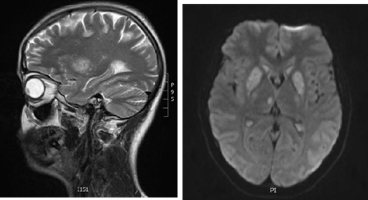

During the stay, the patient received diazepam and dexamethason for three days. The epileptic seizure did not recur; the involuntary movements decreased significantly. After six days, the patient was transferred to the Pathology of Pregnancy Ward, where she stayed for seven days and was discharged home. After a week, more generalized seizures took place, and speech disorders of dysarthria appeared. Laboratory tests revealed a reduced level of ionized calcium and an increased value of D-Dimers. Tetany test-positive. Another MRI scan of the head with angiography showed: hyperintense signals within the deep nuclei and significant impairment of blood flow in the internal veins of the brain. The image suggested cerebral vein thrombosis (Figure 2). Anticoagulant therapy (enoxaparin) and antiepileptic therapy (levetiracetam) were started. No clotting disorders were found. The pregnancy was terminated by cesarean section at 37 weeks. After delivery, anticoagulant therapy (enoxaparin) was continued at a therapeutic dose for another three months, after which the drug was discontinued. Antiepileptic treatment was also discontinued. In the follow-up MR examination after three months, further regression of changes was observed. Six months after delivery, the patient was in good condition without any complaints and any neurological symptoms. She is cared for under constant neurological supervision.

Figure 2 Angio - MRI scan of the head. Hyperintense signals within the deep nuclei and significant impairment of blood flow in the internal veins of the brain.